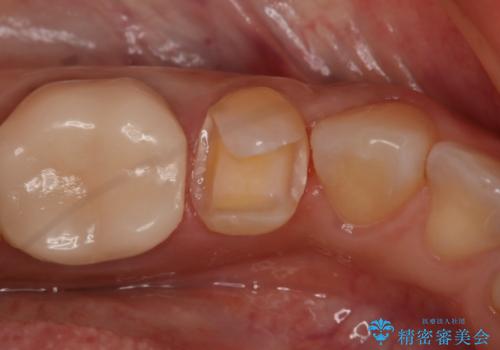

- 左下5番の銀歯をセラミックにやり変え希望の患者様です。

切削量を考慮し、セラミックインレーでの治療を選択しました。

銀歯直下のう蝕を除去しCRで裏層を行った上で、形成・印象を行っています。